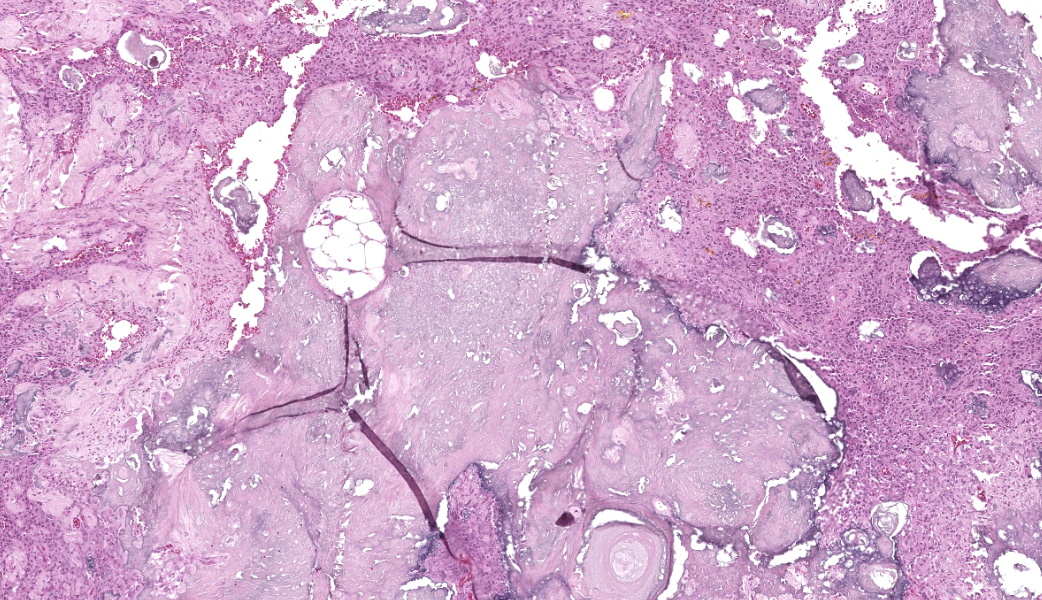

The affected skeletal muscle and subcutis were infiltrated and expanded by abundant, irregular, globoid amphophilic to basophilic material, consistent with mineralization. This mineralized material was surrounded by extensive fibrous connective tissue proliferation (fibrosis), admixed with numerous macrophages, lymphocytes, and fewer multinucleated giant cells containing phagocytosed mineral material. Scattered throughout the mass, rare foci of osteoid formation were observed, characterized by a low number of empty lacunae and necrotic osteoids undergoing remodeling. Multifocally within the mineralized soft tissue lesions, multiple tortuous blood vessels with thickened tunica media were observed. Additionally, there were areas of extensive hemorrhage, neovascularization, and granulation tissue formation infiltrating and replacing the surrounding adipose tissue.

Histologically, calcinosis circumscripta is characterized by aggregates of amorphous to granular, lightly to deeply basophilic mineralized material. These deposits are typically surrounded by macrophages, multinucleated giant cells, and occasional lymphocytes, and are delineated by fibrous connective tissue bands. As the lesion progresses, mineralization becomes more extensive and is accompanied by pronounced fibrosis. The associated inflammatory response may diminish over time, and areas of osseous or cartilaginous metaplasia may develop. In certain cases, epidermal sequestration or transepidermal elimination of mineralized material may lead to ulceration.2,3,4